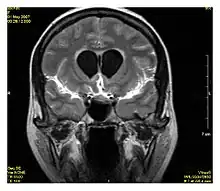

La séquence Fluid-attenuated inversion recovery (FLAIR) est une séquence IRM en inversion récupération qui annule le signal des fluides. Cette séquence est généralement utilisée pour l'IRM cérébrale pour supprimer le signal du liquide cérébrospinal (LCS), ce qui permet de mieux observer certaines pathologies, notamment celles présentes à l'interface parenchyme-LCS[1],[2]. La séquence fut développée dans les années 1990 par l'équipe de recherche de Hammersmith (constituée de Graeme Bydder, Joseph Hajnal, et Ian Young[3].

La séquence FLAIR est particulièrement utile dans l'évaluation et l'étude des troubles du système nerveux central (SNC), notamment [4]:

- L'accident vasculaire cérébral (AVC)

- Sclérose en plaques (SEP)

- Hémorragie sous-arachnoïdienne

- Les traumatismes crâniens

- Méningite